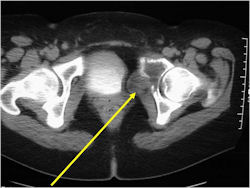

Radiographic Presentation

- Permeative or moth eaten bone destruction

- Ill defined and malignant appearing

- Bony changes are often subtle

- Soft Tissue Mass in 90% of of cases

- Periosteal Reaction in 50% of cases

- Pelvis